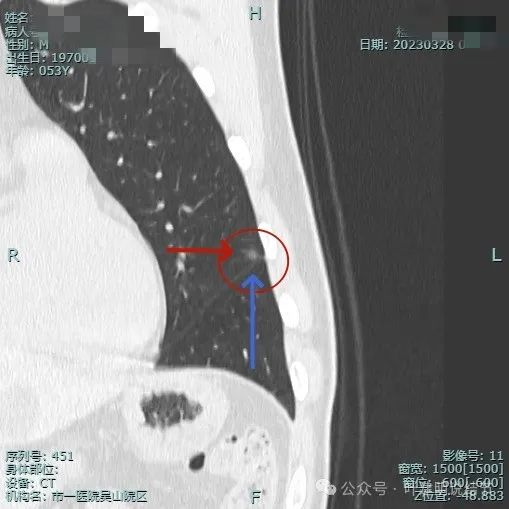

靶重建后见病灶密度不是很淡,轮廓较清,离叶间裂近但未见明显牵拉。

上图层面病灶贴着叶间裂,轮廓与瘤肺边界清楚,表面不光滑。

病灶似有极微细血管进入,贴着叶间胸膜但没有牵拉或明显凹陷。

关键是上图层面怎么贴着叶间裂这侧密度有增高了?偏实性成分!2023年3月时是靶重建情况下都没有见到偏实性成分的。